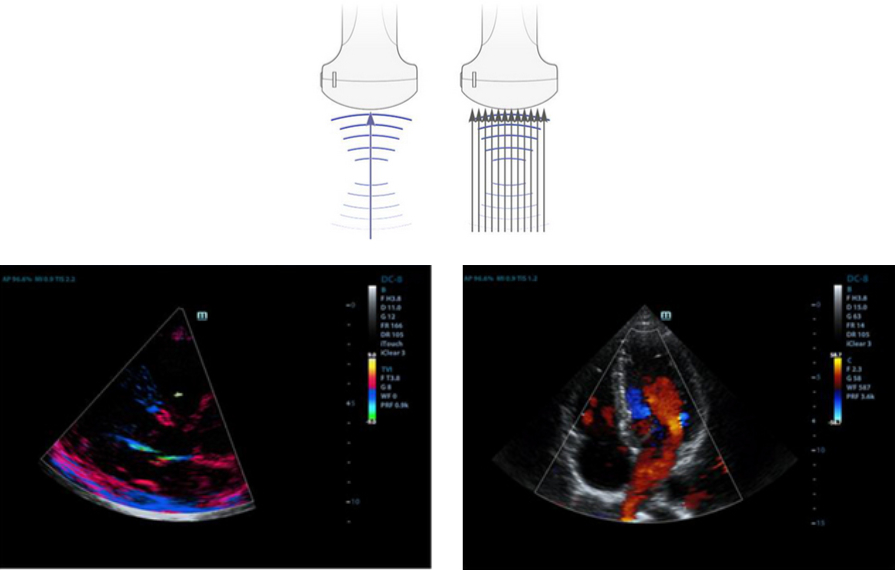

Formación de haces enriquecida por eco

La formación de haces enriquecida por eco permite utilizar las se?ales de eco tradicionalmente ignoradas de los haces adyacentes para formar un haz de imagen más fino y fuerte, lo que permite obtener una mejor resolución de las imágenes "desenfocadas" y una penetración de imagen más profunda.

Formación de varios haces

Un máximo de 12 asignaciones de tarea para un haz transmitido, lo que permite obtener una excelente resolución temporal y una velocidad de imagen más alta.